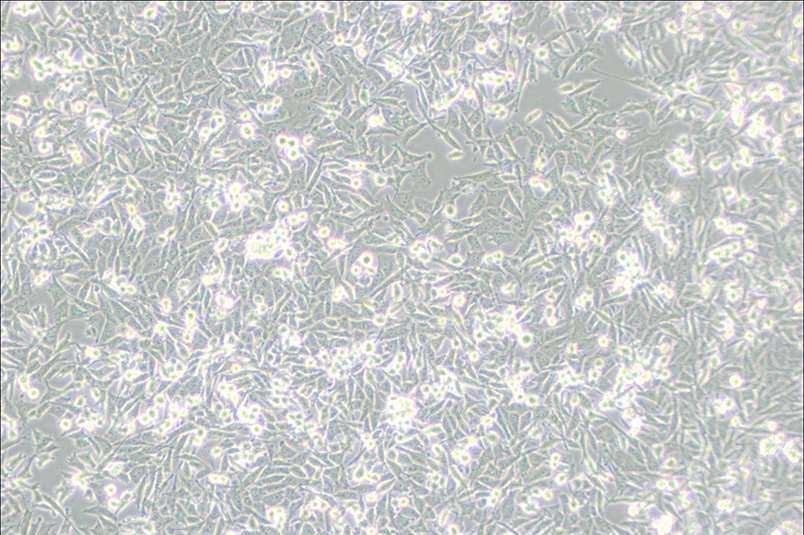

PaTu 8988t人胰腺癌細胞

細胞簡稱 :PaTu 8988t

細胞形態 :上皮細胞樣

生長特性 :貼壁細胞